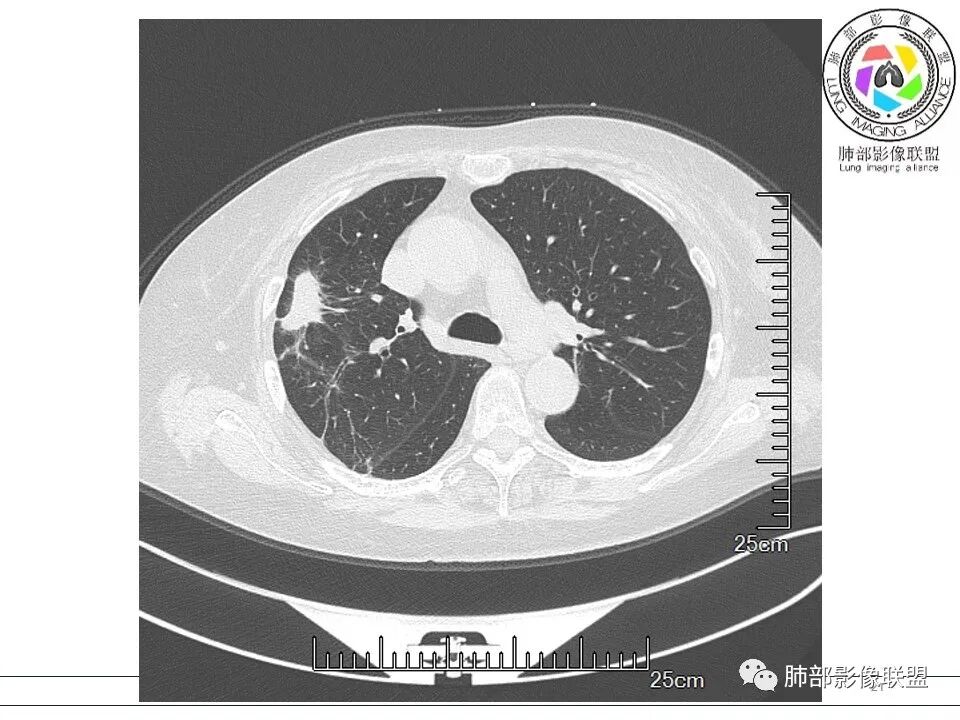

宇宙: 右肺上叶胸膜下结节,多结节融合,长轴平行胸膜,边缘模糊,周围长索条,胸膜牵拉,近端支气管充气扩张,考虑隐球菌,鉴别OP

黄棘: 右肺上叶近胸膜下病灶,多个融合,边缘清,与胸膜平行分布,支气管进入后堵塞,周围见多发长索条影,考虑隐球菌

果哣.: 右肺上叶靠近胸膜结节影,平直为主,边缘清晰,支气管进入后截断,有扩张,考虑炎性隐球菌可能

衡妈: 老年女性,右肺上叶沿胸膜下不规则实性病灶,长轴平行于胸膜,有结节融合感,边缘部分彭隆部分平直,周围可见数条纤维灶影,病灶内可见充气支气管征未达远端,首诊考虑慢性炎性肉芽肿,隐球菌?机化性肺炎?建议增强扫描及ct下穿刺活检。

放射线 (王秀仙): 右肺上叶胸膜下结节样影,边缘平直收缩,胸膜牵拉,支气管进入病灶并扩张,部分支气管进入后阻塞,长轴平行于胸膜,周围可见片状及条索状影,隐球?机化性肺炎?

良孑: 右肺胸膜下多发结节,长轴与胸膜平行,部分病灶有多结节融合,可见近端支气管充气征,有晕征及晕中软毛刺,长期口服激素病史,抗炎效果欠佳。病灶形态单一,无播散性树芽,结节内无支气管穿行,单侧发病,收缩力差,可排除TB,OP及淋巴瘤,综和考虑支持隐球菌

5、分布:隐球菌肺炎是肺泡性炎症,病灶分布多位于胸膜下,可紧贴胸膜,也可与胸膜邻近,病灶长轴与胸膜平行。(划重点,分布特点非常重要,因为隐球菌如果没有荚膜,会被巨噬细胞吞噬,在人体内是无法生存。隐球菌孢子吸入后,要有高浓度的CO2的条件下,才能形成荚膜,所以肺泡内、胸膜下多见)

10、“葫芦兄弟”:邻近胸膜多发结节,形态接近,排列呈长串状。